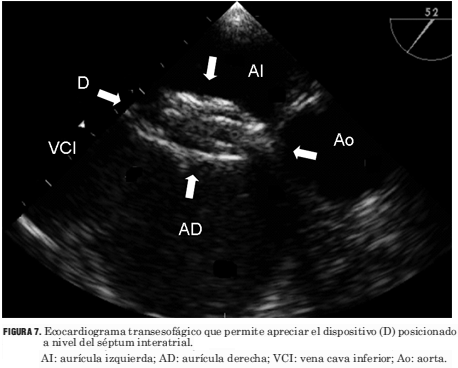

Todos los procedimientos se realizaron bajo anestesia general. En todos los casos se utilizó la vía venosa femoral. Se realizó la medida de la presión arterial pulmonar y cálculo de relación QP/QS (flujo pulmonar/flujo sistémico) mediante oximetrías. Se efectuó angiografía de vena pulmonar superior derecha en oblicua anterior izquierda con la finalidad de determinar las características anatómicas de la CIA y del séptum interauricular (figura 3). Posteriormente se efectuó la insuflación de un catéter balón medidor, con medio de contraste diluido (figura 4), posicionado a nivel del defecto interatrial hasta que cesa el flujo a su través, valorado por el Doppler color en el ETE (figura 5). Ello permite realizar la medida del diámetro de la CIA y elegir el diámetro del dispositivo. Los dispositivos utilizados fueron en tres casos el Cardioseal y en 72 el Amplatzer ASO. Todos los procedimientos fueron realizados con ETE simultáneo con el que se verificó la correcta ubicación del dispositivo antes y después de su liberación, y se descartó el compromiso de estructuras vecinas (figuras 6 y 7).

Figura 7. Ecocardiograma transesofágico que permite apreciar el dispositivo (D) posicionado a nivel del séptum interatrial. AI: aurícula izquierda; AD: aurícula derecha; VCI: vena cava inferior; Ao: aorta.